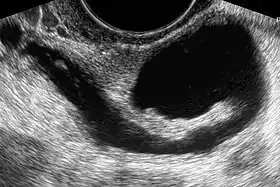

The presence of a hydrosalpinx by sonography indicates distal tubal obstruction

While a full testing of tubal functions in patients with infertility is not possible, testing of tubal patency is feasible. A hysterosalpingogram will demonstrate that tubes are open when the radioopaque dye spills into the abdominal cavity. Sonography can demonstrate tubal abnormalities such as a hydrosalpinx indicative of tubal occlusion. During surgery, typically laparoscopy, the status of the tubes can be inspected and a dye such as methylene blue can be injected in a process termed chromotubation into the uterus and shown to pass through the tubes when the cervix is occluded. Laparoscopic chromotubation has been described as the gold standard of tubal evaluation.[3] As tubal disease is often related to Chlamydia infection, testing for Chlamydia antibodies has become a cost-effective screening device for tubal pathology.[3]

While IVF therapy has largely replaced tubal surgery in the treatment of infertility, the presence of hydrosalpinx is a detriment to IVF success.[5] It has been recommended that prior to IVF, laparoscopic surgery should be done to either block or remove hydrosalpinges.[11]